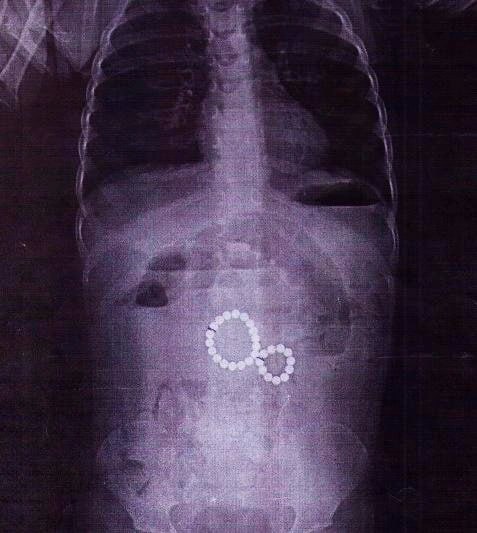

Сначала врачи поликлиники подозревали у ребёнка энтеровирус, но состояние ухудшилось: появилась непроходимость, сильная боль и рвота с кровью.

Рентген показал, что магниты соединились в «восьмёрку» и повредили кишечник, вызвав перитонит. Хирурги удалили все инородные тела и устранили осложнения. Сейчас малышка идёт на поправку.